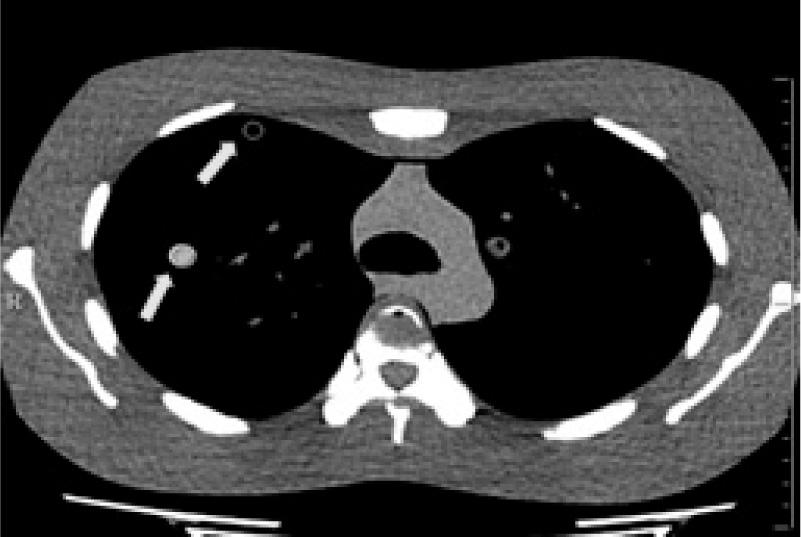

This study was approved by the institutional review board (IRB) of the Faculty of Medicine, Chulalongkorn University (certificate of approval No. 140/2013; IRB No. 078/56). A multipurpose anthropomorphic chest phantom model N1 Lungman (Kyoto Kagaku, Japan) was used to simulate a standard human chest. This phantom is an accurate life-size anatomical model of a human torso. The inner components of the phantom consist of mediastinum, pulmonary vasculature, abdominal block, and synthetic bones that have x-ray attenuation rates relatively to those of human tissues (Figure 1A). To mimic pulmonary lesions, five sizes of spherical simulated nodules of 12, 10, 8, 5, and 3 mm in diameters with a CT number of 100 Hounsfield Units (HU) (Figure 1B) were attached into the lung field of the chest phantom, i.e. right upper lobe (12 mm), central of left upper lobe (10 mm), right lower lobe (8 mm), 1/3 in peripheral of left lower lobe (5 mm), and central of right middle lobe (3 mm) respectively.

Figure 1

The inner components of the LUNGMAN phantom, B: Various sphere sizes of simulated lung nodules of 3, 5, 8, 10, and 12 mm in diameter